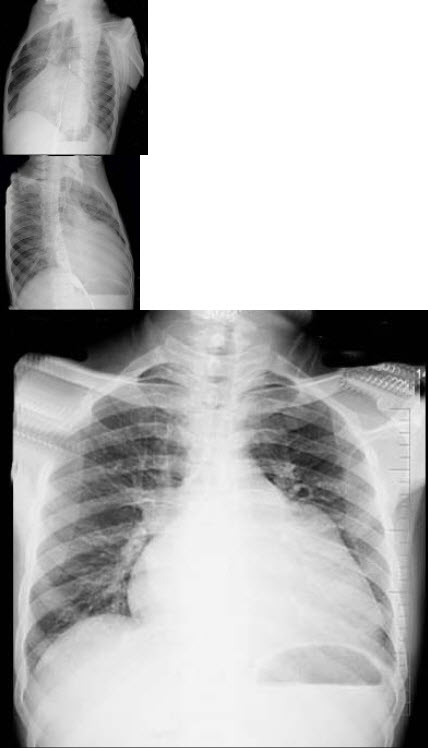

56岁男性患者,劳累后心慌气促10余年,近来自觉症状加重。临床听诊,心尖区有舒张期隆隆样杂音,行胸部X检查,如图所示,你认为下列描述正确的是( )

A:考虑二尖瓣狭窄

B:右前斜位示左心房增大,心后上缘后突压迫冲钡食管

C:左前斜位示心影向后下方突出

D:考虑三尖瓣狭窄

A:后前位示双侧肺血增多,肺动脉段隆起,左心缘出现第3弓

E:考虑二尖瓣狭窄